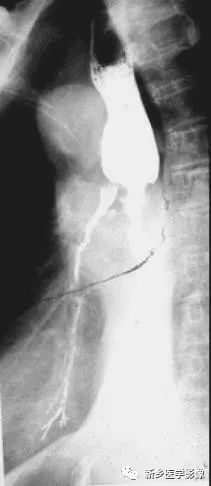

中段食管癌并发食管气管瘘钡餐造影图像

吞钡后食管中段狭窄,并见支气管显影